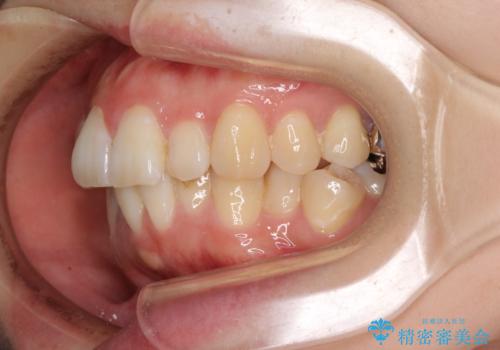

目立たない裏側装置でデコボコをきれいに解消

第二小臼歯抜歯としたため、治療期間は長くなりましたが、満足のいく仕上がりとなりました。